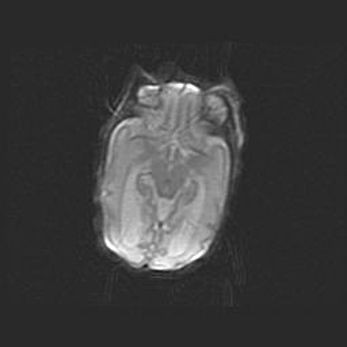

Мальформация Денди-Уокера. Киста задней черепной ямки.

Агенезия мозолистого тела.

Возраст: 2,5 месяца

Вес: 2420 г

Пол: женский

Окружность головы: 37 см

Срок гестации: 32 недели

Мальформация Денди—Уокера — редкий вид патологии ЦНС, представляющий собой врожденный порок развития каудального отдела ствола и червя мозжечка, ведущий к неполному раскрытию срединной (Мажанди) и латеральных (Лушка) апертур IV желудочка мозга. Для этогно синдрома характерна триада симптомов: гипотрофия червя мозжечка и/или полушарий мозжечка, кисты задней черепной ямки, гидроцефалия различной степени. В 70% случаев порок сочетается и с другими аномалиями головного мозга, в частности с агенезией мозолистого тела.